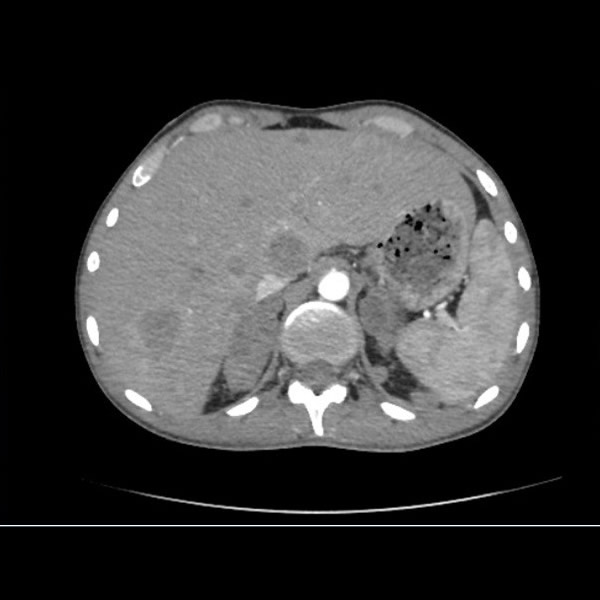

Septiembre 2019. Nuevo Hospital San Roque Sexo: masculino Edad: 26 años MC: dolor en región lumbar izquierda